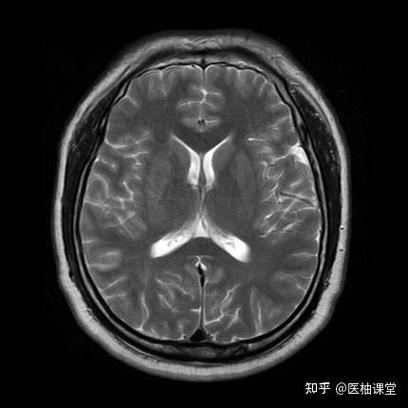

正常脑CT(作为对照)

- 图示:头骨(白)轮廓清晰,脑组织(灰)均匀,脑室(黑)对称。

- 正常,未见明显异常。